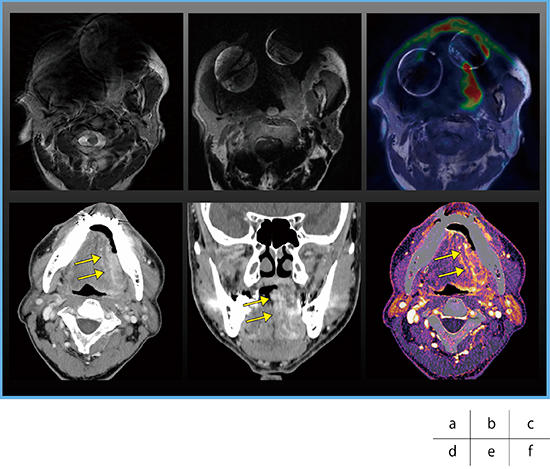

症例3は左舌縁がんの症例であるが,インプラントによる金属アーチファクトの影響により,MRIのみでは同定が困難だった(図7 a,b)。PET/MRIでは腫瘍に一致したFDG集積を認めた(図7 c)。SEMARを適用した造影CTでは,金属アーチファクトが問題になることなく,腫瘍の深達度診断が可能であった(図7 d,e)。さらに,CE Boost画像では,より明瞭に腫瘍を描出できた(図7 f)。

図7 症例3:左舌縁がん(T3)

a:MRI(T2WI) b:MRI(T2WI+Gd) c:PET/MRI

d,e:超高精細CT(SEMAR) f:CE Boost画像